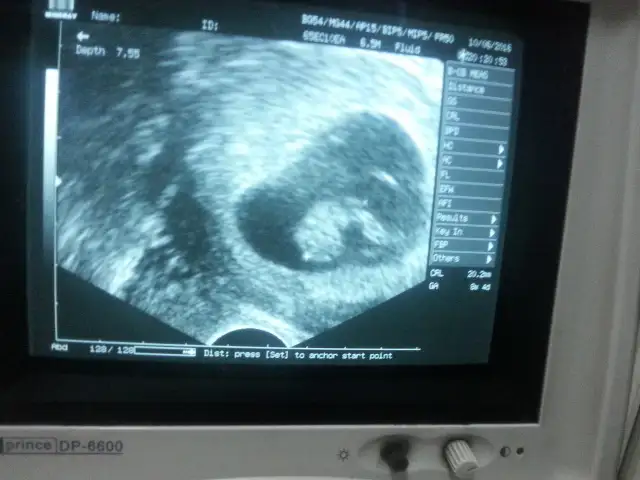

Bebeğin kesedi konumu teorisi tuttum canım sağlıkla kucaklaTahmini olan var mi acaba ? :)

Havalianne__ . bana da yorum yapar mısın 8 ve 12 haftalık goruntuler.Karından usg ikisi de

6+0 vajinal 8+0 karından 8+2 vajinal

Eki Görüntüle 1846894 Eki Görüntüle 1846895 Eki Görüntüle 1846896